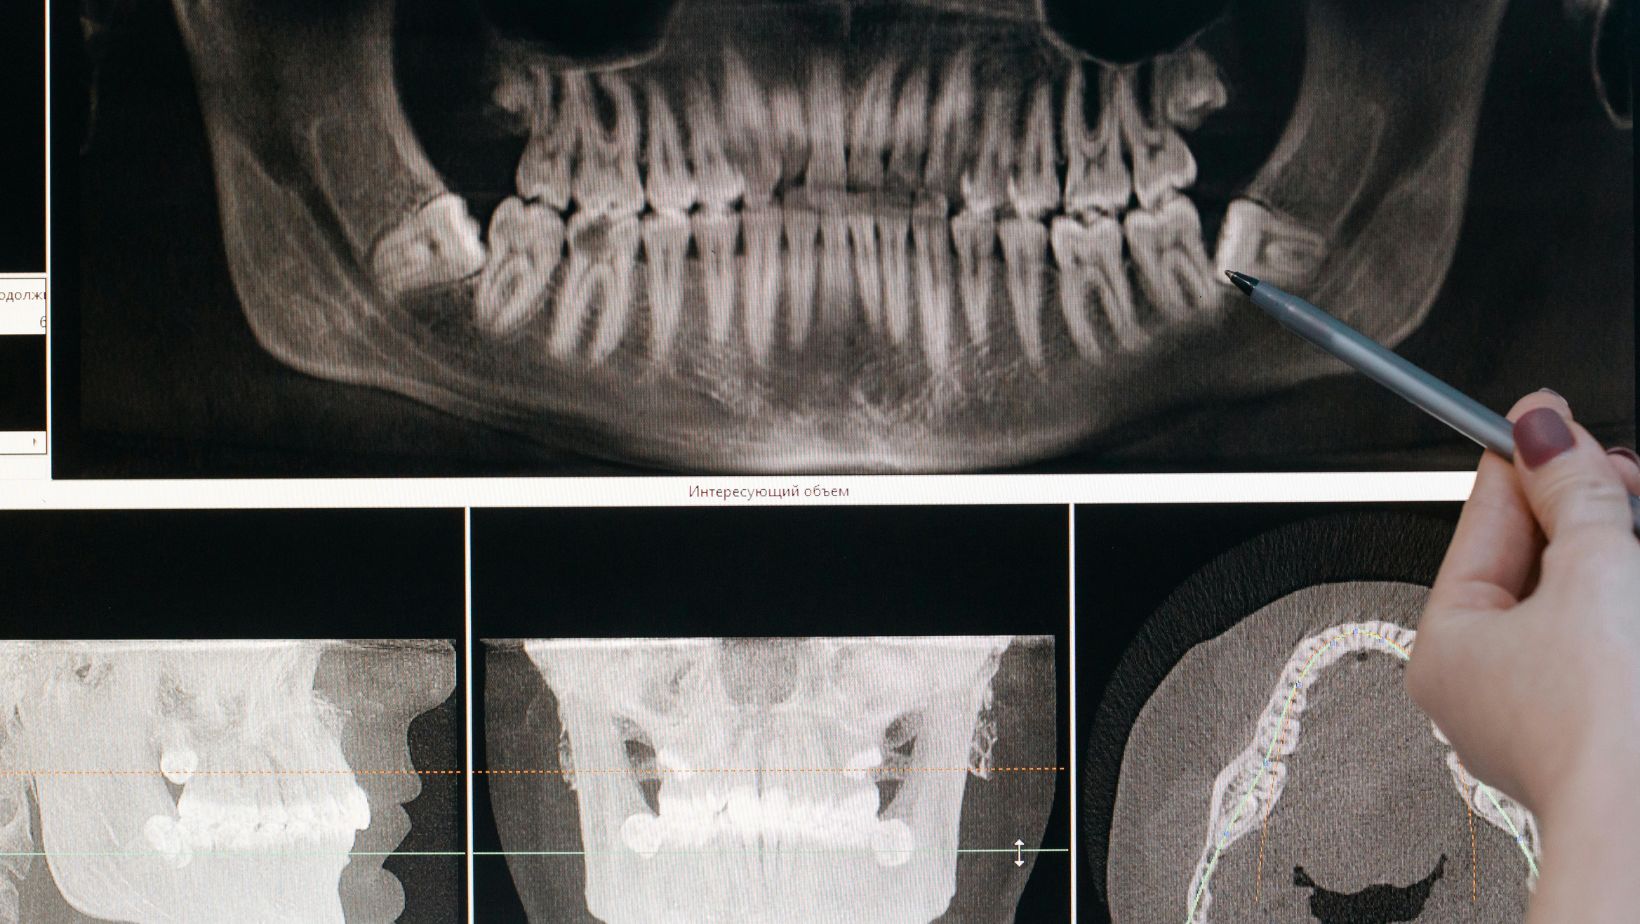

During your consultation at CU Dentists in Champaign IL, your dentist will examine your mouth, take X-rays or scans, and discuss all available treatment options. The goal is to find a solution that balances comfort, aesthetics, and long-term health.